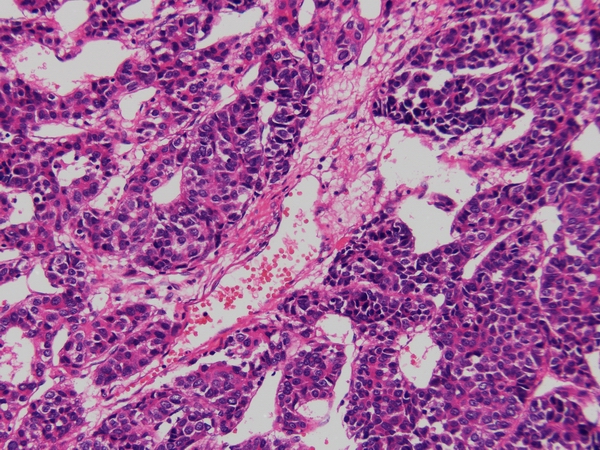

原发性肝细胞癌Glypican-3 染色,胞质阳性

HE染色